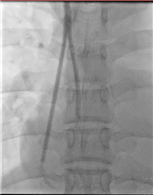

透视下导管位置良好

长期血液透析导管置入术是在介入导管室进行,在DSA影像引导下行右颈内静脉、上腔静脉血管造影,血管通畅,引入血液透析导管,导管远端达理想位置后,将导管缝合固定于右上胸壁。术后即可经右颈内静脉长期血透导管引血,进行血液透析治疗。